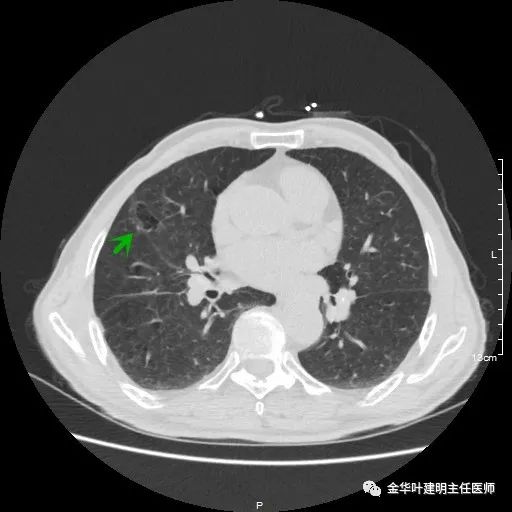

以上示右下叶病灶5。也是主病灶,是实性块状分叶的占位性病变,基本可以肯定是肺癌。单病灶看需下叶切除并清扫淋巴结。

以上示右下叶病灶6。同样是囊腔型病灶,但较前几个范围小,可囊壁同样为磨玻璃影,也是较为典型的囊腔型肺癌表现,单灶来看可下叶背段切除。